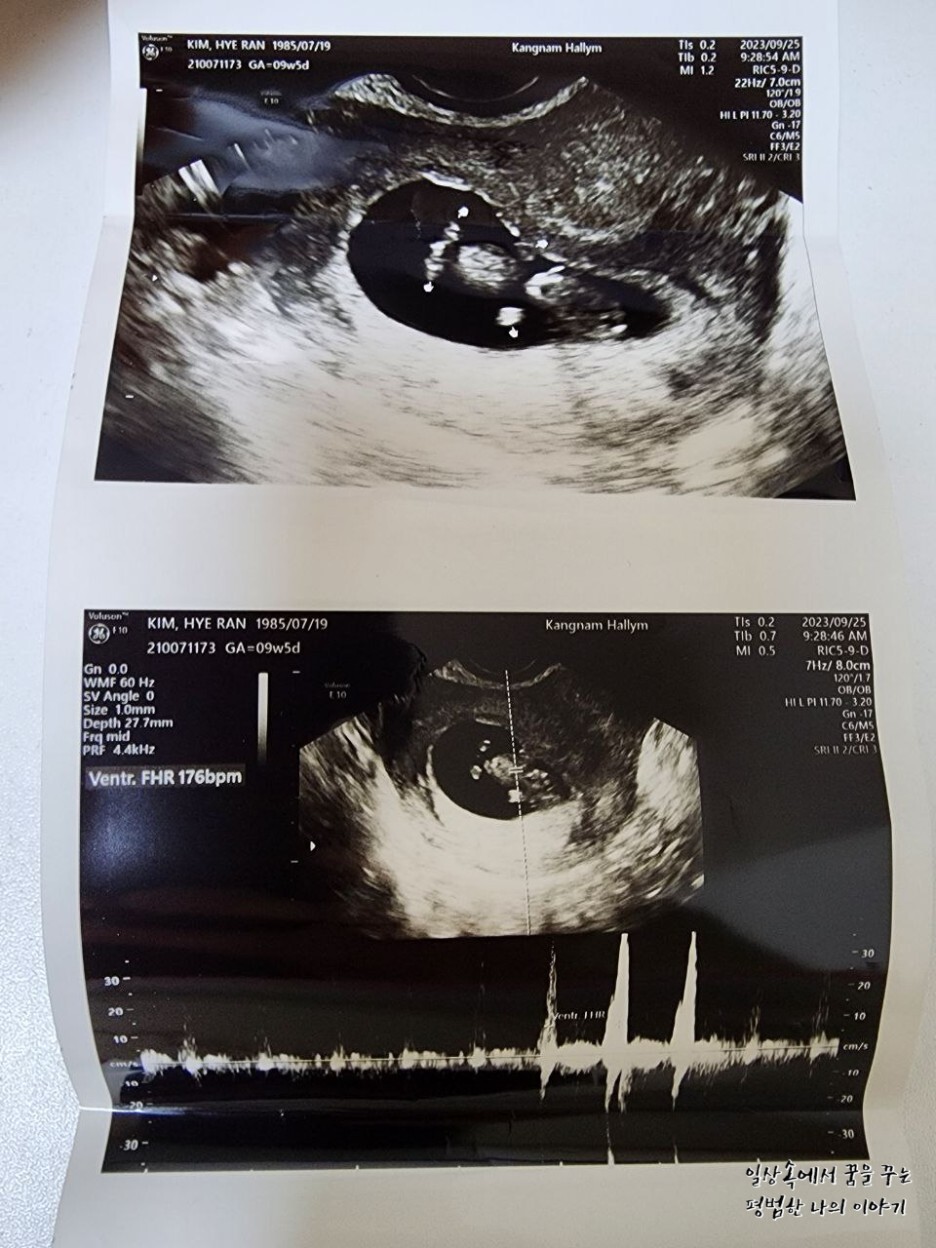

2023년 9월 25일(월요일)

FHR(Fetal Heart Rate, 심장박동 수): 176bpm

소견: 무척 활발해서 한시도 가만히 있지 않음

2주 만에 만난 레오나는 여전히 내 눈에 귀여운 젤리 곰 형태를 하고 있었다. 2주 사이에 16.72mm에서 31.71mm로 두 배나 길어져 있었다. 31.71mm라고 해봐야 정말 콩알만 한 크기이지만 그 작은 크기에도 얼굴, 손 그리고 발까지 초음파로 확인이 가능하다. 출산 예정일은 지난번에 비해 3일 앞당겨졌는데 아기의 크기에 따라 계속 바뀔 수 있으므로 대략 4월 셋째 주쯤 출산하겠구나 예상하고 계획을 짜기 시작했다.